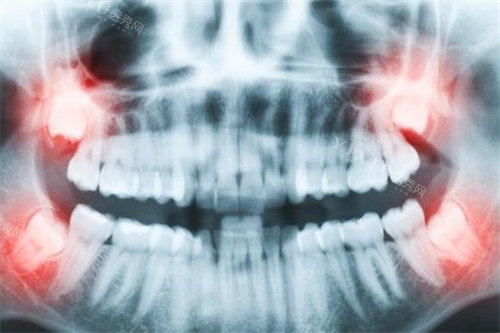

准备好既往牙科治疗记录和X光片

种植牙对医生技术要求较高,不妨多比较几家诊所的方案,了解所使用种植体品牌及医生相关资质。